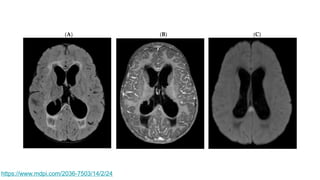

https://www.mdpi.com/2036-7503/14/2/24